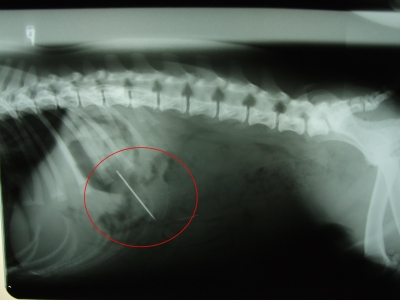

NIE KAŽDÝ CUDZÍ PREDMET MUSÍ KONČIŤ NA CHIRURGICKOM STOLE

Pred mesiacom k nám prišiel majiteľ so psíkom - plemeno francúzsky buldoček ktorý tvrdil, že pes mu práve prehltol ihlu. U psíka sme chceli potvrdiť alebo vyvrátiť majiteľové tvrdenie o prehltnutí cudzieho predmetu, preto sme vykonali rtg vyšetrenie. To nám potvrdilo, že skutočne psík má v žalúdku krajčírsku ihlu. Po zvážení situácie, jej rizikách sme sa rozhodli pre konzervatívnu liečbu u psíka, t.j. čakať. Každý deň sme u psíka rentgenovali dutinu brušnú, kontrolovali celkový klinický stav a podávali stravu overenú i u ľudí pri podobných prípadoch - kyslá kapusta s varenými zemiakmi. Cudzí predmet - ihla - vycestovala z psíka za 48hodín po prehltnutí. Tento prípad a veľa ďalších v praxi dokazuje, že nie všetky zjedené cudzie predmety musia končiť chirurgickým zákrokom.

rtg snímka 1 hodina po prehltnutí

rtg snímka - 24hodín po zjedení bočná projekcia

rtg snímka - 24 h po zjedení d-v projekcia

rtg snímka - 48 h po zjedení, ihla lokalizovaná v dolnom úseku hrubého čreva